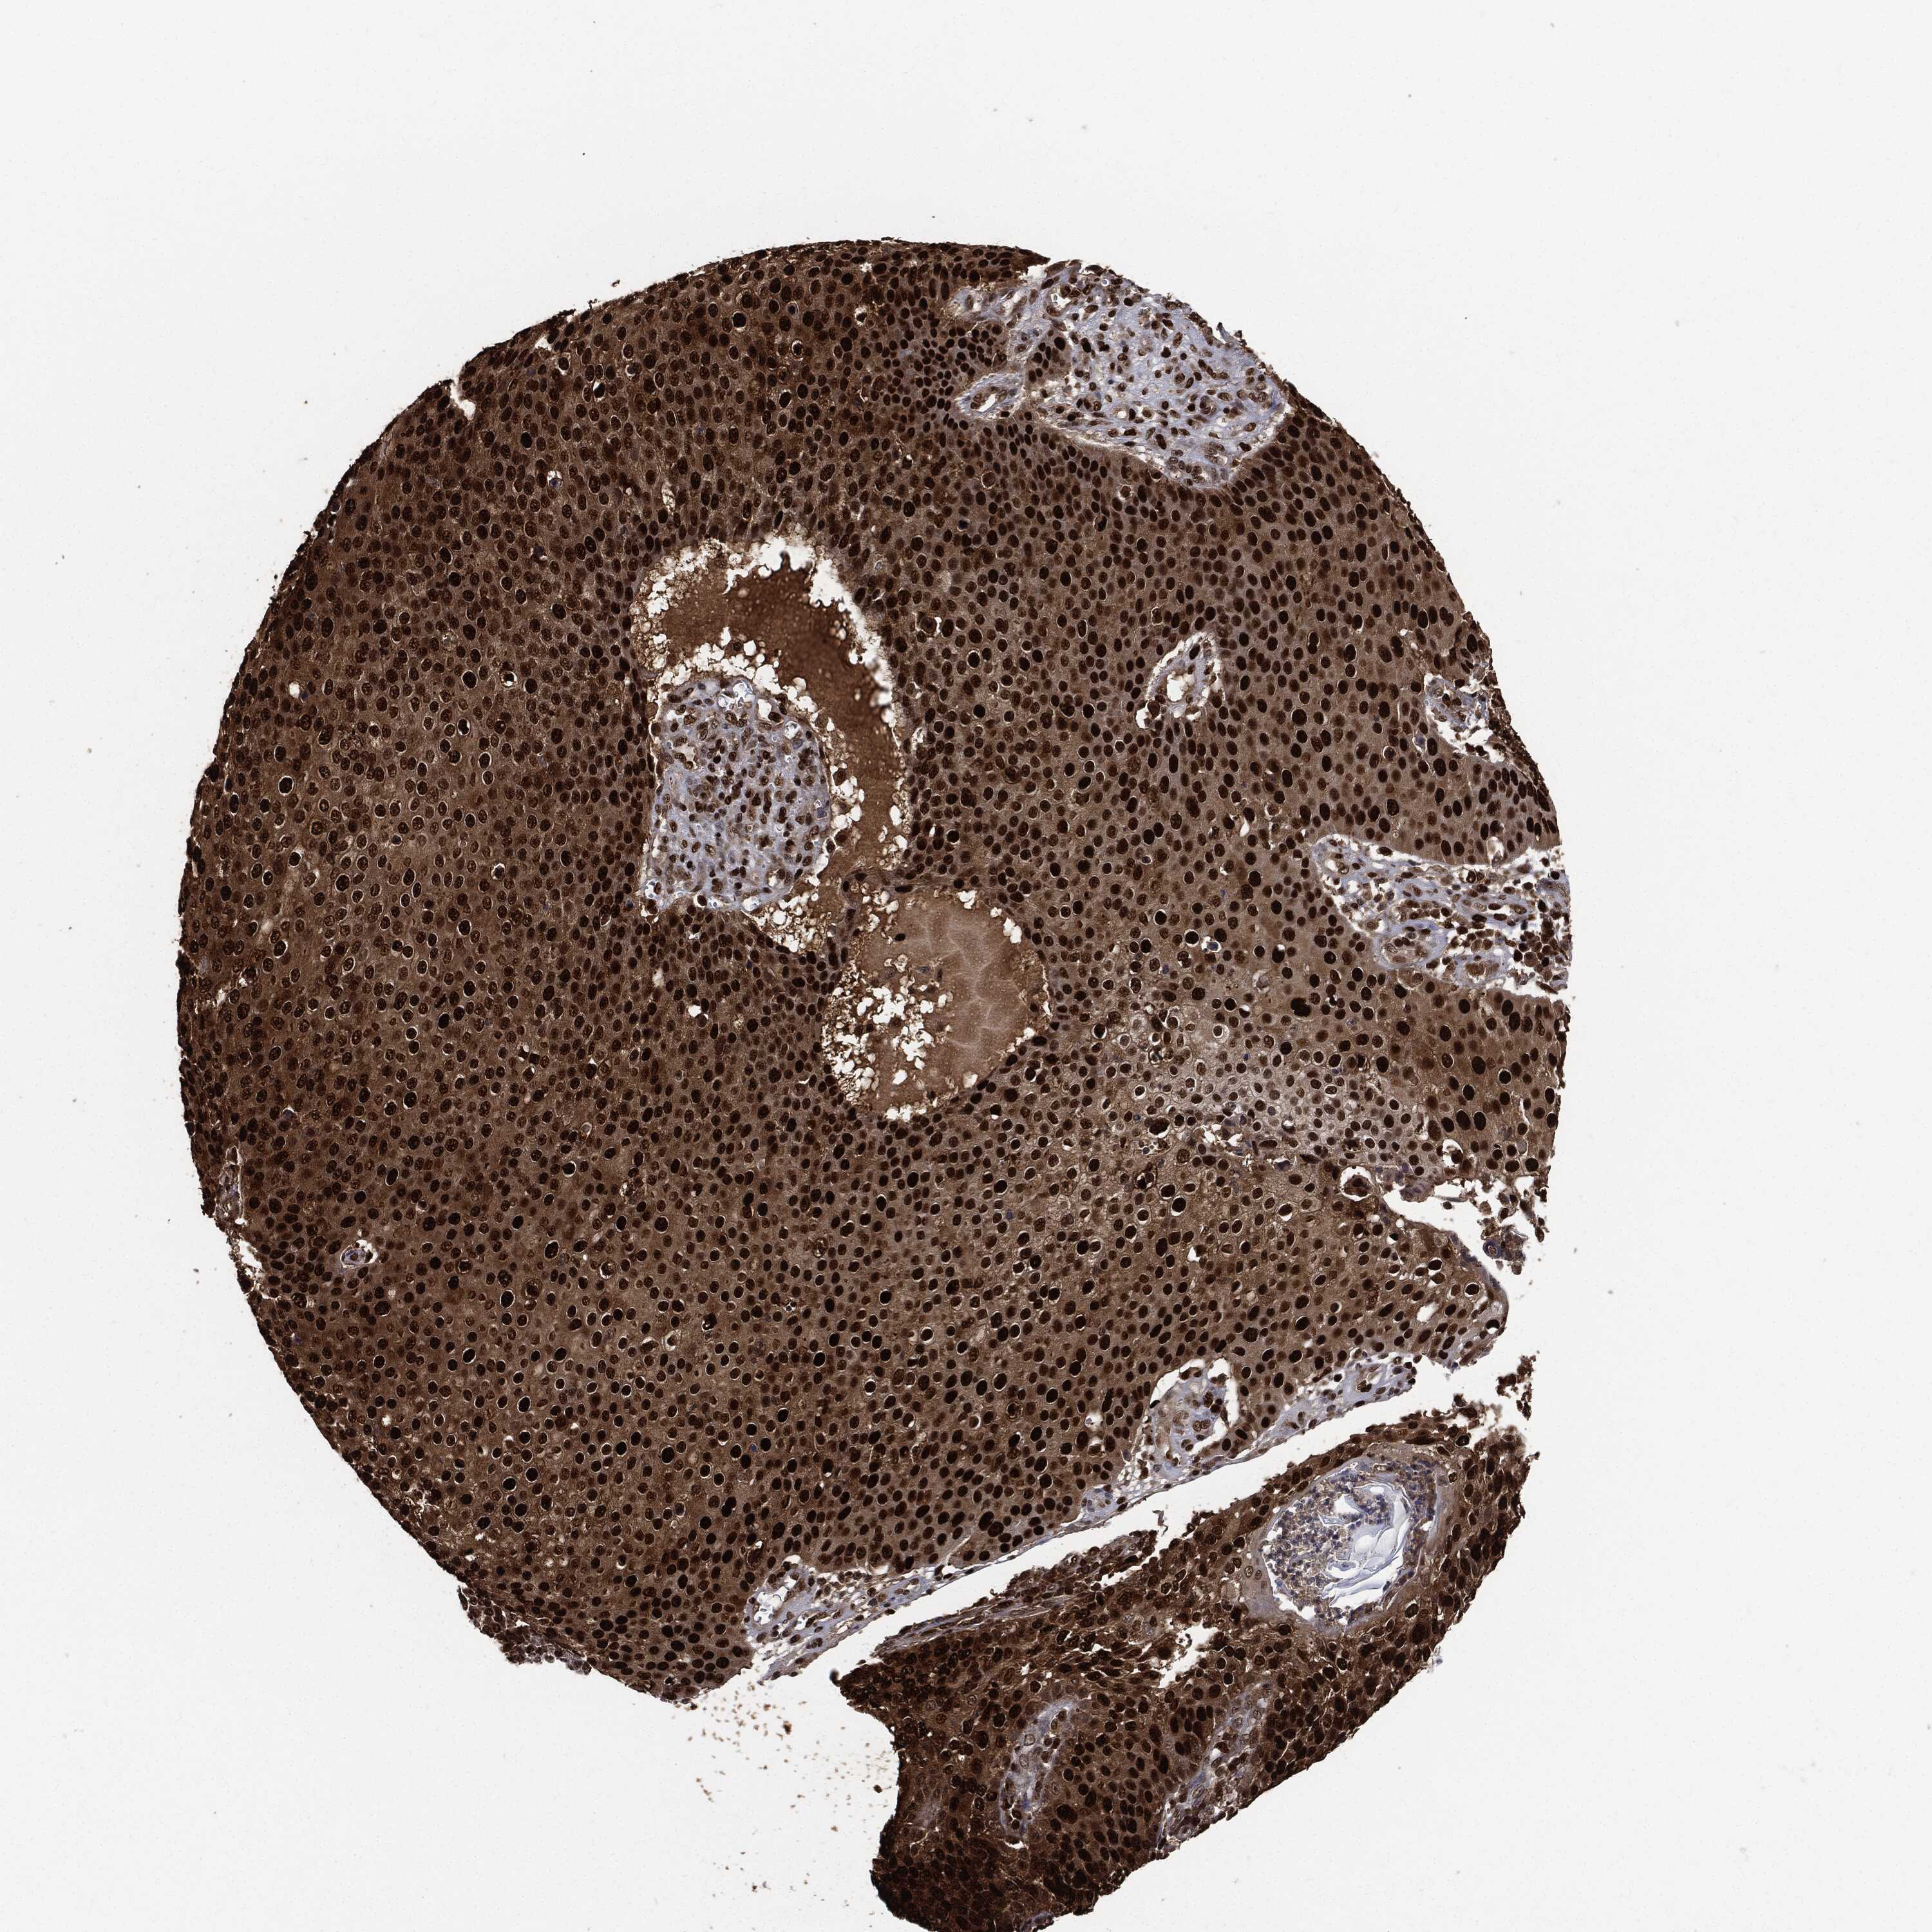

SKIN CANCER - Protein expressioni

A mouse-over function shows sample information and annotation data. Click on an image to view it in a full screen mode. Samples can be filtered based on level of antibody staining by selecting one or several of the following categories: high, medium, low and not detected. The assay and annotation is described here.

Each image is clickable and will lead to virtual microscopy that enables deeper exploration of all samples and also displays staining intensity scores, fraction scores and subcellular localization as well as patient and tissue information for each sample.

HPA030521

HPA030522

HPA030523

CAB000148

CAB080240

CAB080241

CAB080242

Staining

High

Medium

Low

Not detected

Intensity

Strong

Moderate

Weak

Negative

Quantity

>75%

75%-25%

<25%

None

Location

Nuclear

Cytoplasmic/membranous

Cytoplasmic/membranous,nuclear

Basal cell carcinoma

Squamous cell carcinoma, NOS

Squamous cell carcinoma, metastatic, NOS